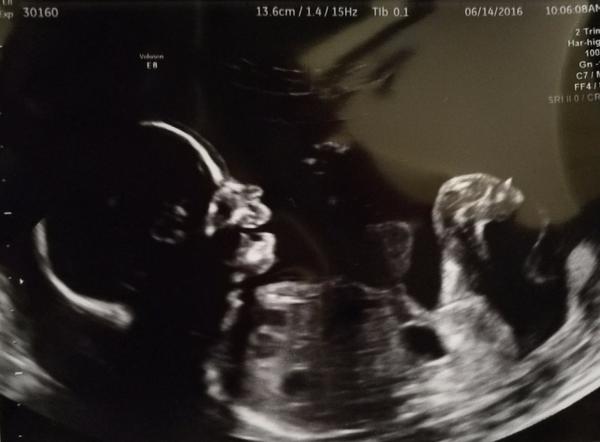

Ahoj, už nevím kam bych se na internetu podívala po jménu pro holčičku. Chtěli bychom něco neobvyklého, svátek aby měla nejlépe někdy v létě, asi spíš kratší jméno. Aby nebylo zdrobnělé, ale dalo se různě skloňovat. A nejlépe aby začínalo na A nebo na K. Prosím pište jen jména, ať to nemusím hledat v diskuzi. Děkuji moc 🙂 Posílám fotku naší malé princezny, jak se na nás smála na UZ 🙂